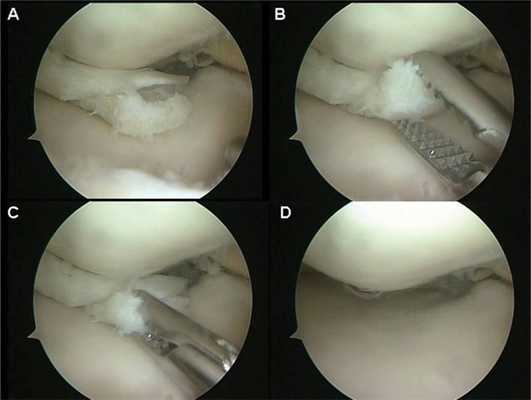

1. Артроскопическая частичная менискэктомия показана пациентам с дислоцированными или нестабильными повреждениями менисков, при которых не может быть выполнен шов мениска (например, повреждения в белой зоне, сегментарные или сложные разрывы менисков) и которые сопровождаются локальной болезненностью в соответствующей области суставной щели коленного сустава и механической симптоматикой, включающей щелчки, заклинивание или блокирование сустава

2. С морфологической точки зрения выделяют радиальные (рис. 1, А), горизонтальные (рис. 1, Б), вертикальные (или продольные, рис. 1, В), в виде «клюва попугая» (рис. 1, Г), «ручки лейки» (рис. 1, Д) и дегенеративные или комплексные разрывы менисков (различные плоскости разрыва, измененная ткань мениска, рис. 1, Е)

• Шов мениска и частичная менискэктомия не являются взаимоисключающими вмешательствами, их можно и нужно комбинировать друг с другом с целью максимально возможного сохранения функции мениска.

• Избыточная менискэктомия или менискэктомия, выполняемая без должных на то показаний, при клинически значимых разрывах менисков может привести к ускоренному износу суставного хряща и усилению болевого синдрома, особенно в наружном отделе коленного сустава

• Неадекватная визуализация или неправильная интерпретация комплексных разрывов менисков, особенно таких, которые включают сегментарный компонент или разрыв в виде «клюва попугая», может привести к тому, что выполненная резекция мениска окажется недостаточной, и болевой синдром или механические симптомы у пациента останутся